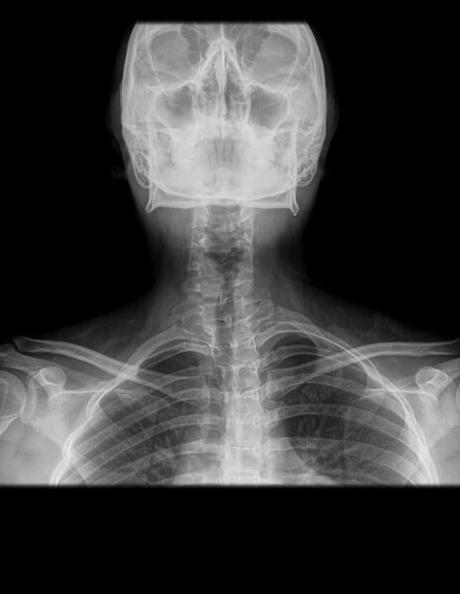

RADIOGRAFIA AP Y LATERAL DE COLUMNA CERVICAL

HALLAZGOS:

-Tejidos blandos, con densidad y morfología respetada, sin evidencia de lesiones.

-Cuerpos vertebrales, con leve angulación hacia derecha. Existe desplazamiento anterior de C3 y C4, menor 25%. Lordosis cervical, rectificada.

-En lo observado de senos paranasales y celdillas mastoideas con adecuada neumatización.

-Estructuras óseas observadas de cráneo sin evidencia de lesiones líticas, blásticas o perdida de la contigüidad.

-Adecuada congruencia de articulaciones de Luschka (uncovertebrales) y de las facetas articulares.

-Cuerpos vertebrales con altura preservada, sin evidencia de lesiones líticas, blásticas o perdida de la contigüidad. Con presencia de algunos osteofitos marginales en C5.

-Plataformas, con adecuada densidad y morfología.

-Pedículos, laminas posteriores sin evidencias de lesiones líticas, blásticas o perdidas de la contigüidad.

-Espacios intervertebrales, con disminución de su amplitud a nivel de C5-C6 y C6-C7.

-Neuro forámenes, con disminución de su amplitud a nivel de C5-C6 y C6-C7.

-Espacio entre apófisis odontoides y C1, menor de 3 mm.

-En topografía de epiglotis se observa trazo horizontal radiopaco que podría corresponder a restos alimenticios óseos.

OPINIÓN RADIOLÓGICA:

EL PRESENTE ESTUDIO RADIOGRAFICO, CON IMAGEN RADIOOPACA NIVEL DE EPIGLOTIS QUE PODRÍAN SUGERIR RESTOS ÓSEOS INGERIDOS.

ASIMETRÍA ESPINAL DEXTROCONVEXA Y RECTIFICACIÓN DE LORDOSIS CERVICAL.

ANTEROLISTESIS DE C3 Y C4, GRADO I DE MAYERDING.

DISCARTROSIS A NIVEL DE C5-C6 Y C6-C7, ASÍ COMO ESTENOSIS DE NEURO FORÁMENES.